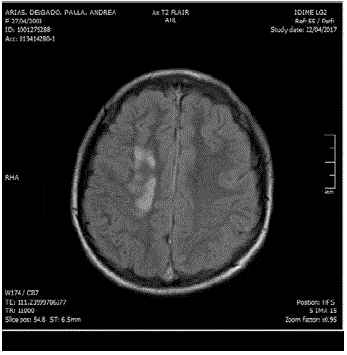

Al ingreso manifestaba intenso dolor cervical, afasia motora, desviación de la mirada a la derecha, sialorrea, hemiparesia izquierda, Babinsky izquierdo, reflejo rotuliano izquierdo exaltado y no mostraba alteración en la sensibilidad ni signos meníngeos. Su talla es de 173 cm (por encima del percentil 95), delgada, extremidades largas y con aracnodactilia. El TAC cerebral simple evidenció trombosis de varios senos venosos (figura 1); el estudio se complementó con Angio TAC cerebral (figura 2), resonancia magnética cerebral (figura 3) y Angio resonancia cerebral contrastada (figura 4), que confirman la trombosis de los senos venosos. Después de diagnosticar accidente isquémico se trasladó a la unidad de cuidados intensivo (UCI) y se anticoagula con enoxaparina. No necesitó soporte inotrópico ni ventilatorio y posteriormente se llevó a pisos. El ecocardiograma y el doppler carotideo fueron normales. No se encontró dislipidemia y el estudio de enfermedad autoinmune fue negativo. Los exámenes para trombofilia, tomados en etapa aguda, solo mostraron una proteína S ligeramente disminuida (57 %, VN de 59 a 118 %), al igual que la antitrombina m (58,8 %, VN 83-128 %). Se ampliaron estudios con ácido fólico y vitamina B12 en sangre, al igual que los ácidos orgánicos en orina por cromatografía; todos estaban normales. Los aminoácidos en sangre mostraron elevación de la metionina (63 µmol/L, VN de 10 a 45 µmol/L) y la homocisteina (3 µmol/L, VN de 0 a 1 µmol/L) con cistationina baja (0, VN de 0 a 3 µmol/L). El estudio de homocisteina en sangre fue de 214 µmol/L (VN en mujer de 5,08 A 15,39 µmol/L), lo que confirmó el diagnóstico de homocistinuria por deficiencia de CBS.